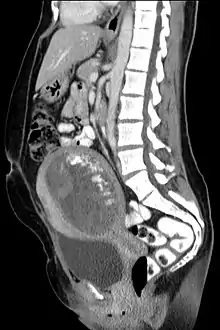

The diagnosis is strongly suggested by ultrasound (sonogram), but definitive diagnosis requires histopathological examination. On ultrasound, the mole resembles a bunch of grapes ("cluster of grapes" or "honeycombed uterus" or "snow-storm").[14] There is increased trophoblast proliferation and enlarging of the chorionic villi, and angiogenesis in the trophoblasts is impaired.[15]

A hydatidiform mole is a pregnancy/conceptus in which the placenta contains grapelike vesicles (small sacs) that are usually visible to the naked eye. The vesicles arise by distention of the chorionic villi by fluid. When inspected under the microscope, hyperplasia of the trophoblastic tissue is noted. If left untreated, a hydatidiform mole will almost always end as a spontaneous abortion (miscarriage).